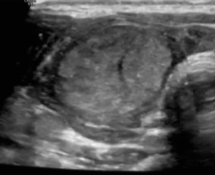

严重并发症【Baek JH 2013】声音改变 结节破裂 结节破裂脓肿形成 甲状腺功能减退 支气管神经丛损伤 ![]() 轻度并发症【Baek JH 2011】血肿 呕吐 皮肤灼伤 发热 典型反应疼痛:是最常见的副作用,2-60%【Nixon IJ 2018】,疼痛可导致2%的治疗停止【Tarantino L 2008】。 可以要求麻醉师在场,或不需要麻醉师,后者可以减少住院话费,也减少麻醉风险。也存在如何维持良好的忍耐性。 ![]() 良好的包膜下麻醉可以减少疼痛